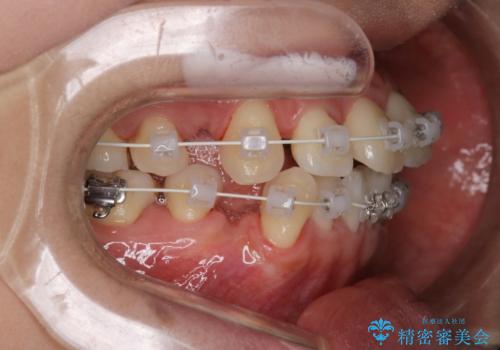

【審美装置】前歯のデコボコを綺麗に

- 上の前歯のデコボコが気になるということで来院されました。

叢生量(デコボコ)が多いため、上下左右4番目の歯を抜歯してワイヤー矯正を行う治療計画を立てました。

主訴である前歯のデコボコが改善され、噛みあわせも綺麗になりました。

歯肉退縮もなく、予定通りに治療を終えることができ良かったです。